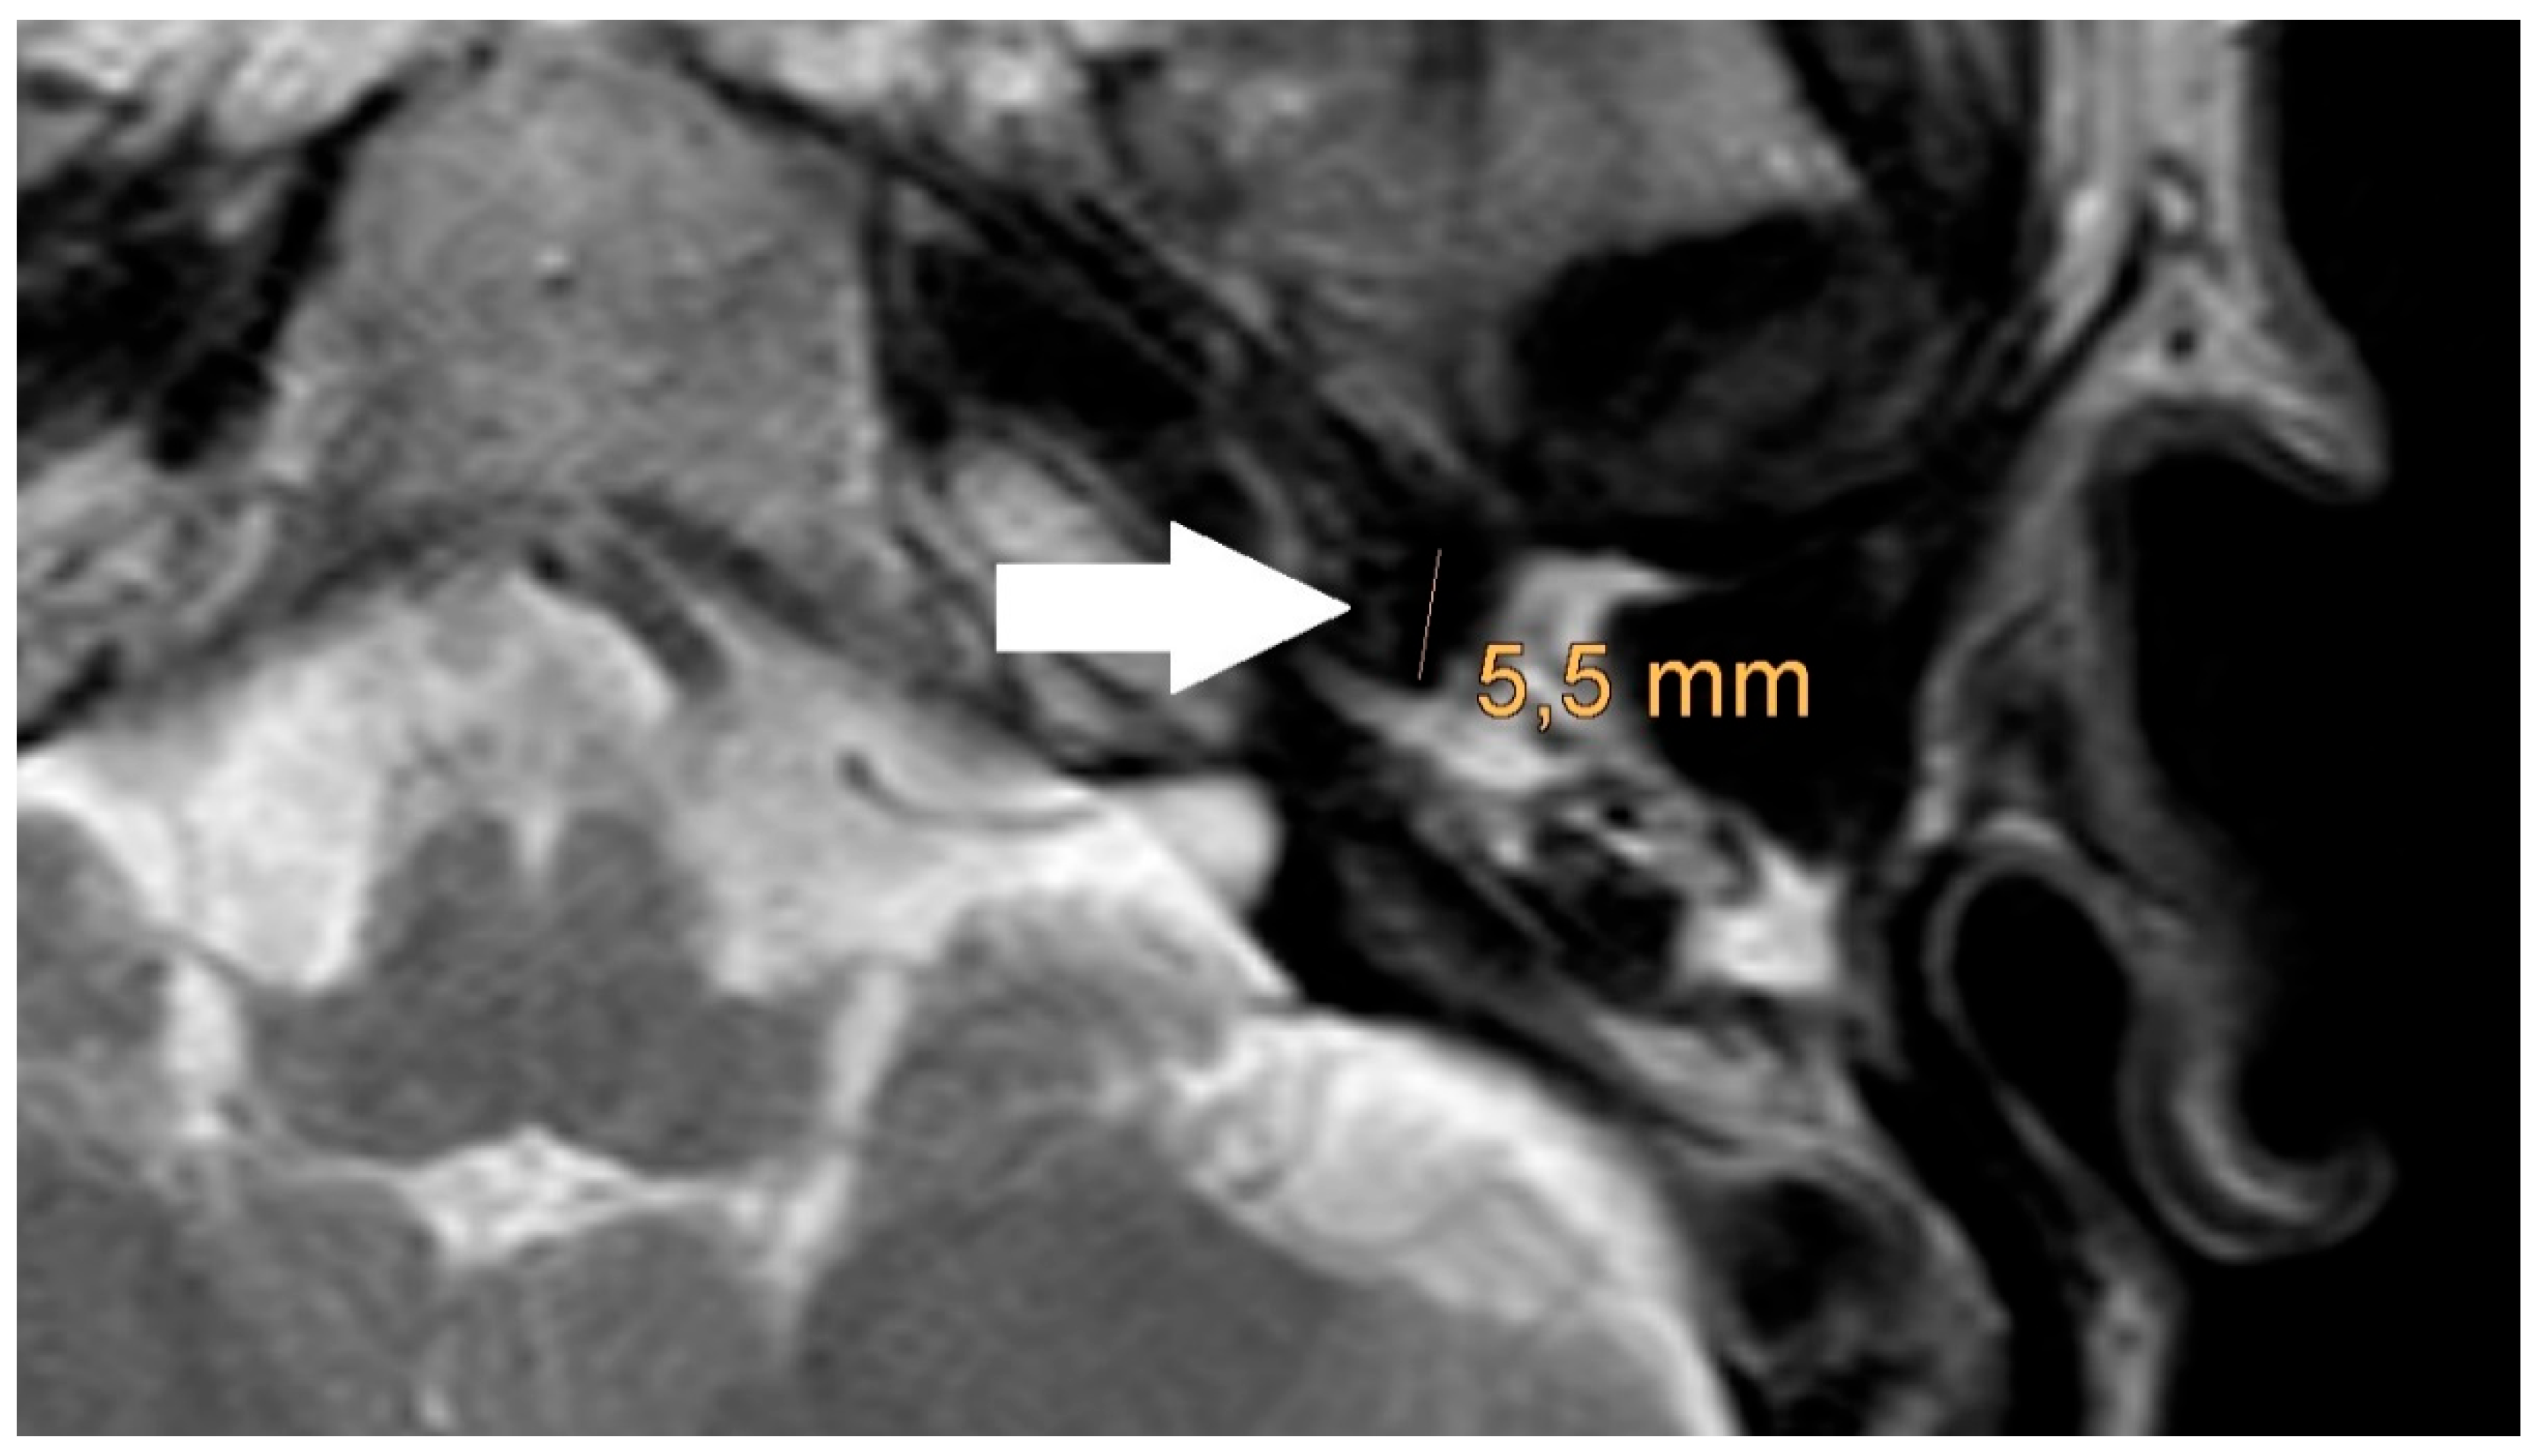

Figure 6. Magnification of the same artifact from Figure 1c with measurement, see white arrow.

The artifact measurements firstly done in T1- or T2-sequence showed an average artifact of 3,1 mm for PORP, 4,7 mm for TORP and 3,6 mm for meshes (see Figure 4, Figure 5 and Figure 6). The overall average artifact was 3,8 mm.

The also done measurement of the artifact for meshes in the non-EPI DWI sequence showed an average artifact size of 5,8 mm (see Figure 3).

The measurement in the non-EPI DWI sequence revealed that the smallest edge length of the voxels in this sequence is 1,9 mm. Ensuing from this the smallest part that can be shown is one voxel (see Figure 3).

The detection rate of a cholesteatoma also depends on the presence of a prosthesis and the proximity of the cholesteatoma to the prosthesis. In our study, the prostheses cause artefacts of at least 2.2 mm in the T1-/T2 sequences. In the non-EPI DWI sequence, the voxel size is 1.9mm and larger than in T1-/T2 sequences. So, to detect a cholesteatoma the cholesteatoma must have a size of larger than 1.9 mm. A cholesteatoma smaller than 1.9 mm which is near to the prosthesis would be covered of the artifact of the prosthesis. Our findings are similar to former studies [18].